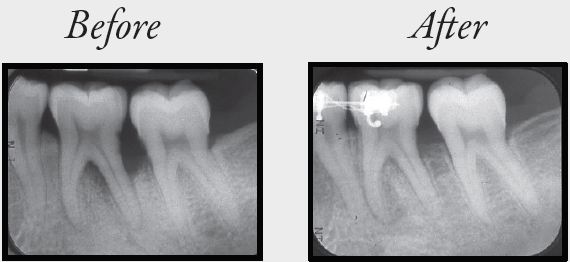

Gum Disease

Gum disease is caused by bacteria (plaque).  In some individuals, plaque can lead to the loss of soft tissue and bony attachment of the tooth to the jaws causing the eventual loss of the tooth.  Risk factors such as smoking and diabetes can progress the rate of destruction at alarming rates.

The base of any treatment is combining professional removal of soft (plaque) and hard (tartar) deposits from below the gum line and ensuring that a patient can perform adequate oral hygiene (brushing and flossing) at home.  Without good home care, professional treatment will not work in the long term!

Once affected areas have been professionally cleaned and a patient is able to perform adequate home care with brushing and flossing, we can correct any significant bone or gum loss around the teeth.